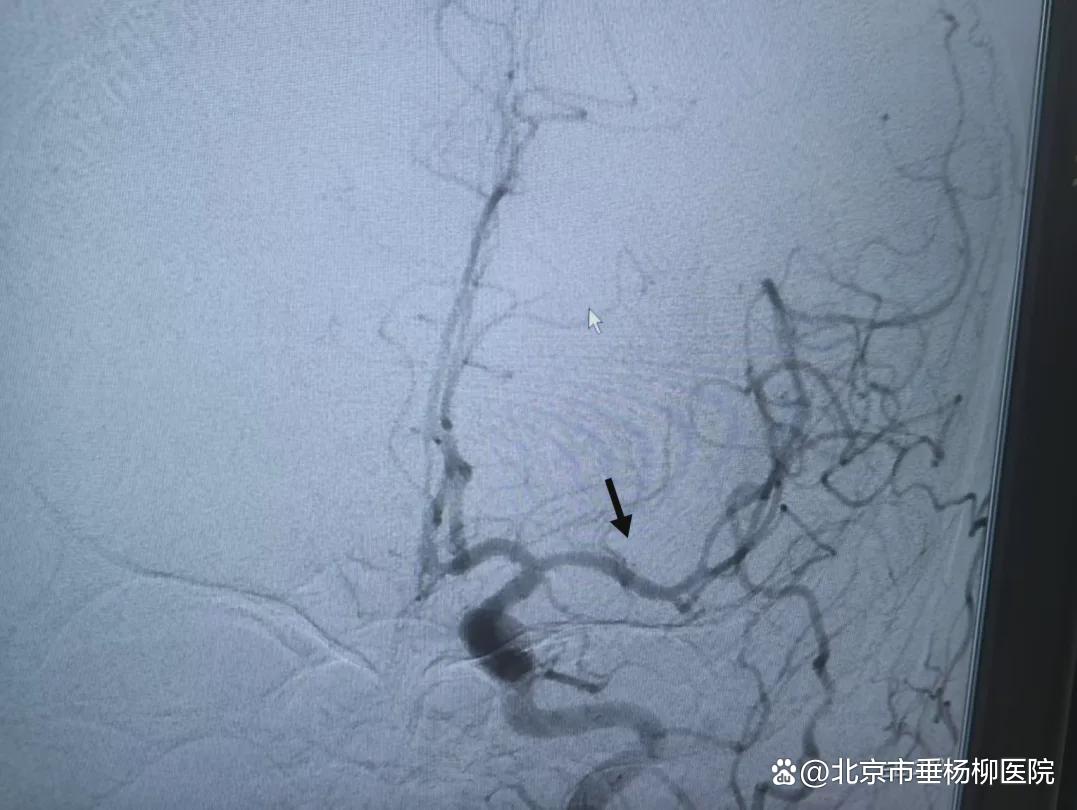

▲术前DSA

然而,经综合评估,考虑造成患者此次脑缺血是因为大血管受累所致,单纯静脉溶栓难以完全开通血管,需急诊桥接动脉取栓。李军立刻联系神经内科介入组副主任医师胡益民、苏杭前来支援。在接到通知后,胡益民、苏杭两位医生纷纷从家中赶赴医院。一场与时间赛跑的战斗就此打响。在三位神经内科专家的强强联手下,患者的手术进展顺利,次日凌晨1:00,患者脑部闭塞的血管被成功开通,复查造影显示远端显影良好。

正当介入团队向患者家属传达手术成功的消息时,120微信群再次传来紧急消息:“冷某某,男,42岁,右侧肢体活动不利,言语不能1小时,到急诊了。”急救的警笛再次响起,李军再次冲向急诊。这位患者偏瘫失语,症状严重,极有可能是大血管病变。李军迅速联系放射科加急进行头颈部CTA检查,结果证实为“左侧大脑中动脉主干闭塞”,同样需要急诊手术。将第一位患者安全转运回病房后,苏杭和胡益民马不停蹄,投入到下一台手术。凌晨4:20,第二位患者的血管也成功开通,术后患者右侧肢体力量即刻有所恢复。在患者家属的感谢声中,三位已经熬红眼的医生终于松了一口气。